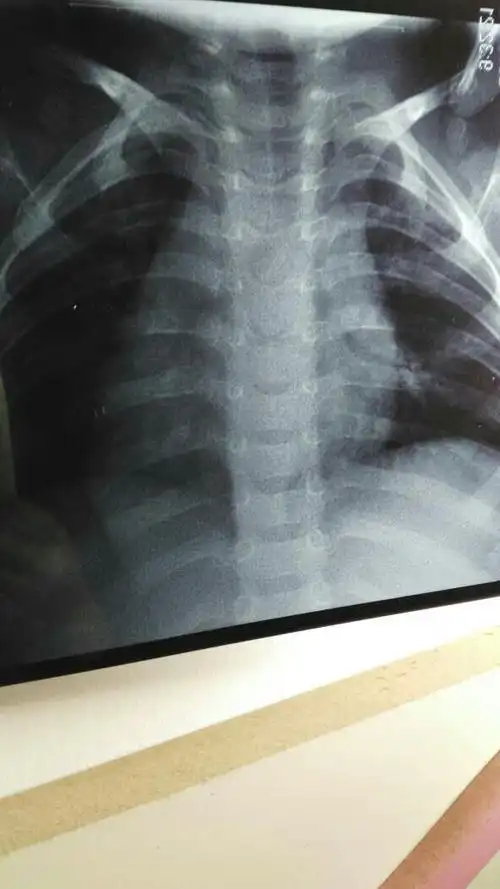

两岁小孩两个月来反复感冒鼻塞咳引起支气管肺炎住,现在又鼻塞咳嗽